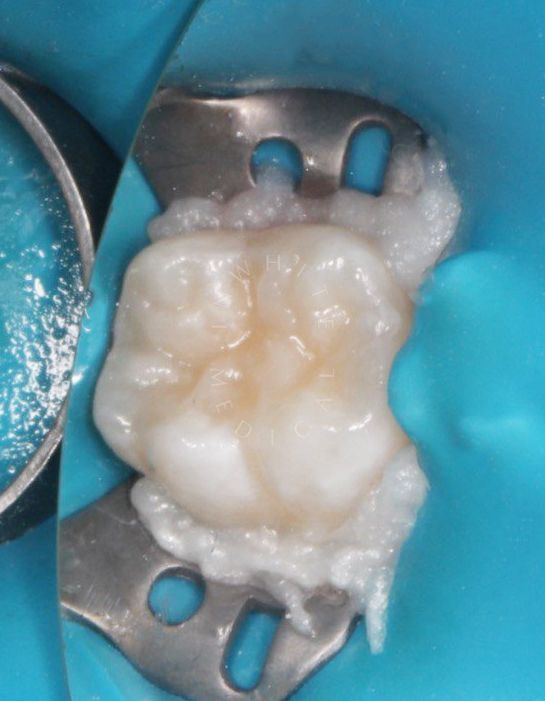

Лечение молочных зубов и установка металлических коронок во сне

Результат